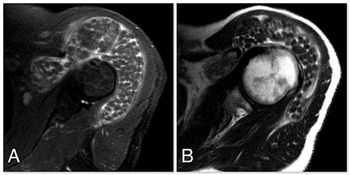

Synovial Osteochondromatosis of Subacromial BursaPublished: July 26th 2013 | Updated: